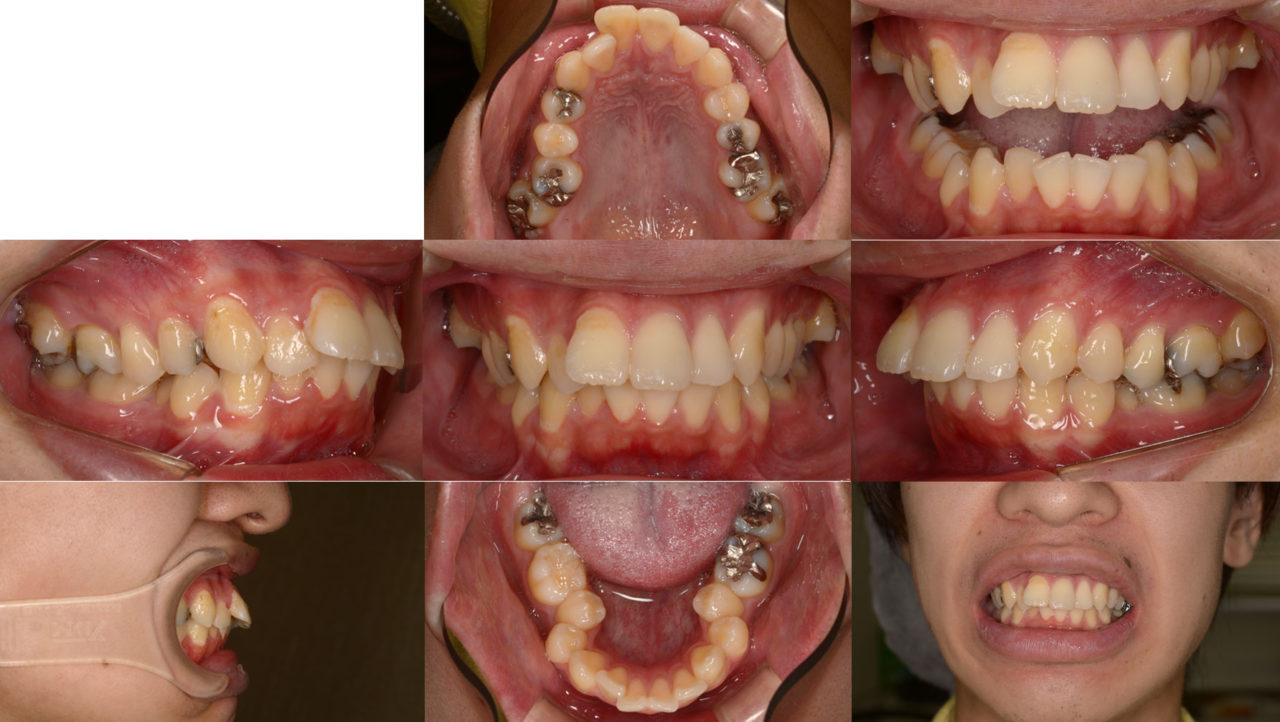

Before

初診 2017.11.2

矯正開始 2018.1.26